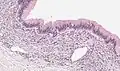

| Micrograph showing a mucinous cystadenoma of the ovary. H&E stain. | |

Mucinous cystadenoma is a benign cystic tumor lined by a mucinous epithelium. It is a type of cystic adenoma (cystadenoma).

PRMC and benign mucinous cystadenoma of the ovary are microscopically similar. Both are multiloculated cystic neoplasms and are lined by a single layer of tall columnar cells with a clear basal nucleus and cytoplasm. Both of them have identical histochemical and ultrastructural features.[9] Flat to low cuboidal cells, resembling mesothelial cells, in the lining interspersed between columnar cells in the same area is the only histological difference between the two tumors.[9]